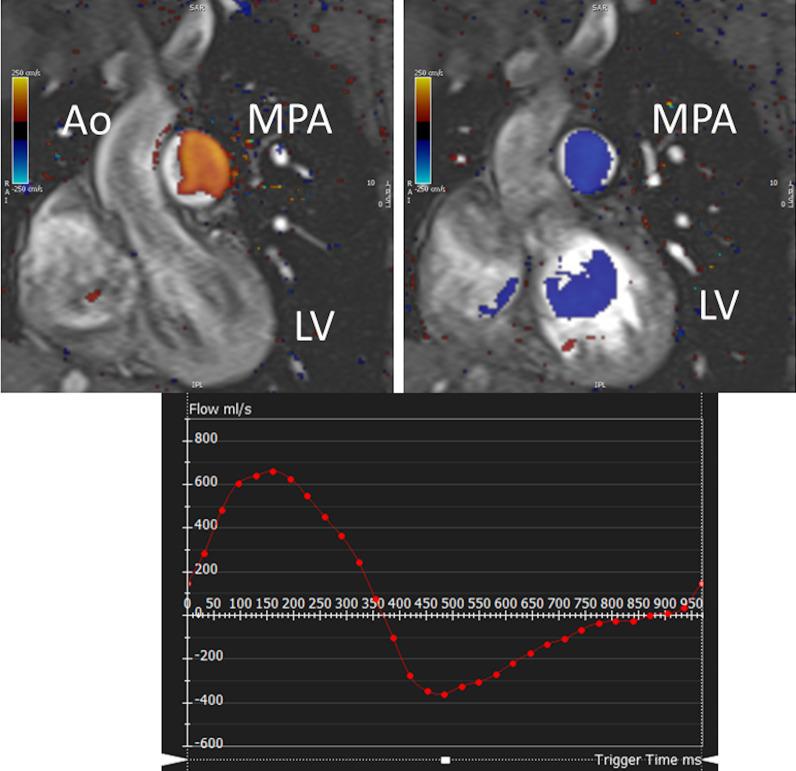

Cardiovascular magnetic resonance (CMR) has been utilized in the management and care of pediatric patients for nearly 40 years. It has evolved to become an invaluable tool in the assessment of the littlest of hearts for diagnosis, pre-interventional management and follow-up care. Although mentioned in a number of consensus and guidelines documents, an up-to-date, large, stand-alone guidance work for the use of CMR in pediatric congenital 36 and acquired 35 heart disease endorsed by numerous Societies involved in the care of these children is lacking. This guidelines document outlines the use of CMR in this patient population for a significant number of heart lesions in this age group and although admittedly, is not an exhaustive treatment, it does deal with an expansive list of many common clinical issues encountered in daily practice.

心血管磁共振(CMR)在儿科患者的管理和护理中已经应用了近 40 年。它已经发展成为评估最小的心脏的宝贵工具,用于诊断、介入前管理和随访。尽管在许多共识和指南文件中提到,但在儿科先天性心脏病和后天性心脏病领域,目前还缺乏一份由众多参与儿童护理的学会共同认可的、最新的、独立的、针对 CMR 使用的大型指南。本指南文件概述了 CMR 在该年龄段的许多心脏病变中的应用,尽管不能说是详尽的治疗方法,但它确实涉及了在日常实践中经常遇到的许多常见临床问题的广泛列表。